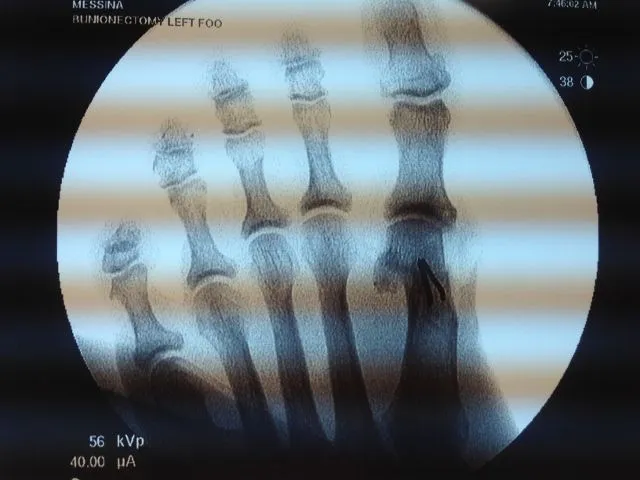

Pre and Postop Xrays

In the x-ray image below is a Hallux Valgus or what is more commonly known as a bunion deformity where the great toe is deviated towards the lesser toes causing abnormal structure which is a result of genetics, abnormal shoegear and abnormal mechanics will cause wearing of the joint and enlargement of the head of the long bone called the first metatarsal.

Post-surgical repair of the same patient bunion deformity with the great toe now in rectus (straight) position with surgically placed screws in the head of the first metatarsal that were used to secure fixation of the cut made across the bone to translate the head of the bone laterally in order to reduce the deformity. The screws will remain in place even after the bone heals.